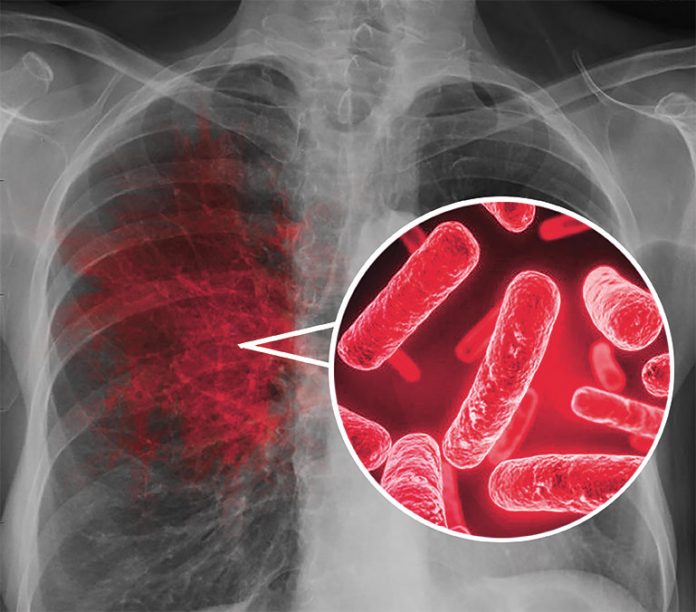

Los casos de tuberculosis respiratoria en México en lo que va de este 2025 serían más de cinco mil, de acuerdo con el Sistema Nacional de Vigilancia Epidemiológica (SNVE), hasta la semana 13 se acumularon cuatro mil 953, de meningitis tuberculosa hay por lo menos 133 y 986 casos de otros tipo de esa enfermedad.

“Los síntomas dependen de la parte del cuerpo afectada, aunque afecta principalmente los pulmones, también puede presentarse en riñones, cerebro, sistema digestivo, columna vertebral y piel. Es una enfermedad infecciosa causada por una micobacteria. Se transmite a través de gotas de saliva suspendidas en el aire cuando una persona que está enferma, tose, escupe o estornuda”, dijo.